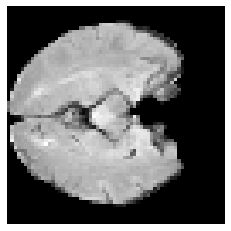

Disentangled representations can be useful in many downstream tasks, help to make deep learning models more interpretable, and allow for control over features of synthetically generated images that can be useful in training other models that require a large number of labelled or unlabelled data. Recently, flow-based generative models have been proposed to generate realistic images by directly modeling the data distribution with invertible functions. In this work, we propose a new flow-based generative model framework, named GLOWin, that is end-to-end invertible and able to learn disentangled representations. Feature disentanglement is achieved by factorizing the latent space into components such that each component learns the representation for one generative factor. Comprehensive experiments have been conducted to evaluate the proposed method on a public brain tumor MR dataset. Quantitative and qualitative results suggest that the proposed method is effective in disentangling the features from complex medical images.